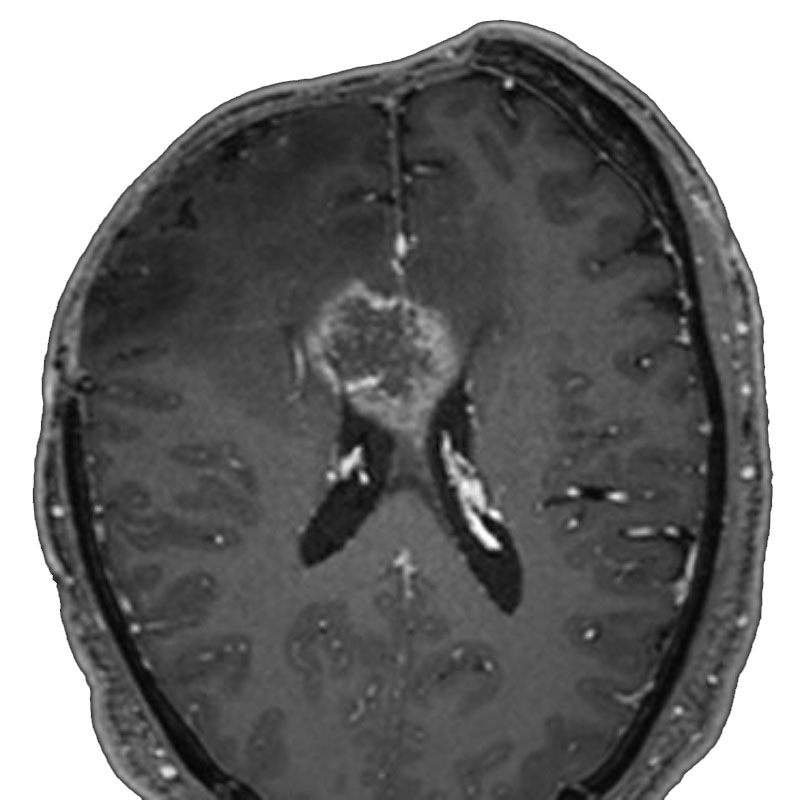

脳室内腫瘍

摘出術

北野/濵田